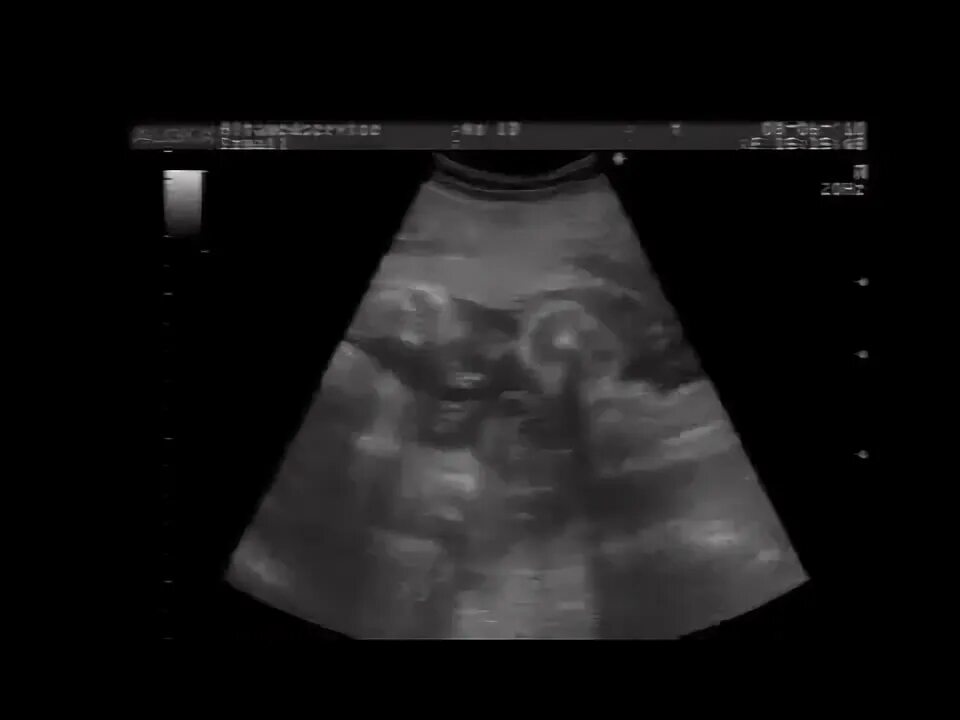

27 недель беременности двойня